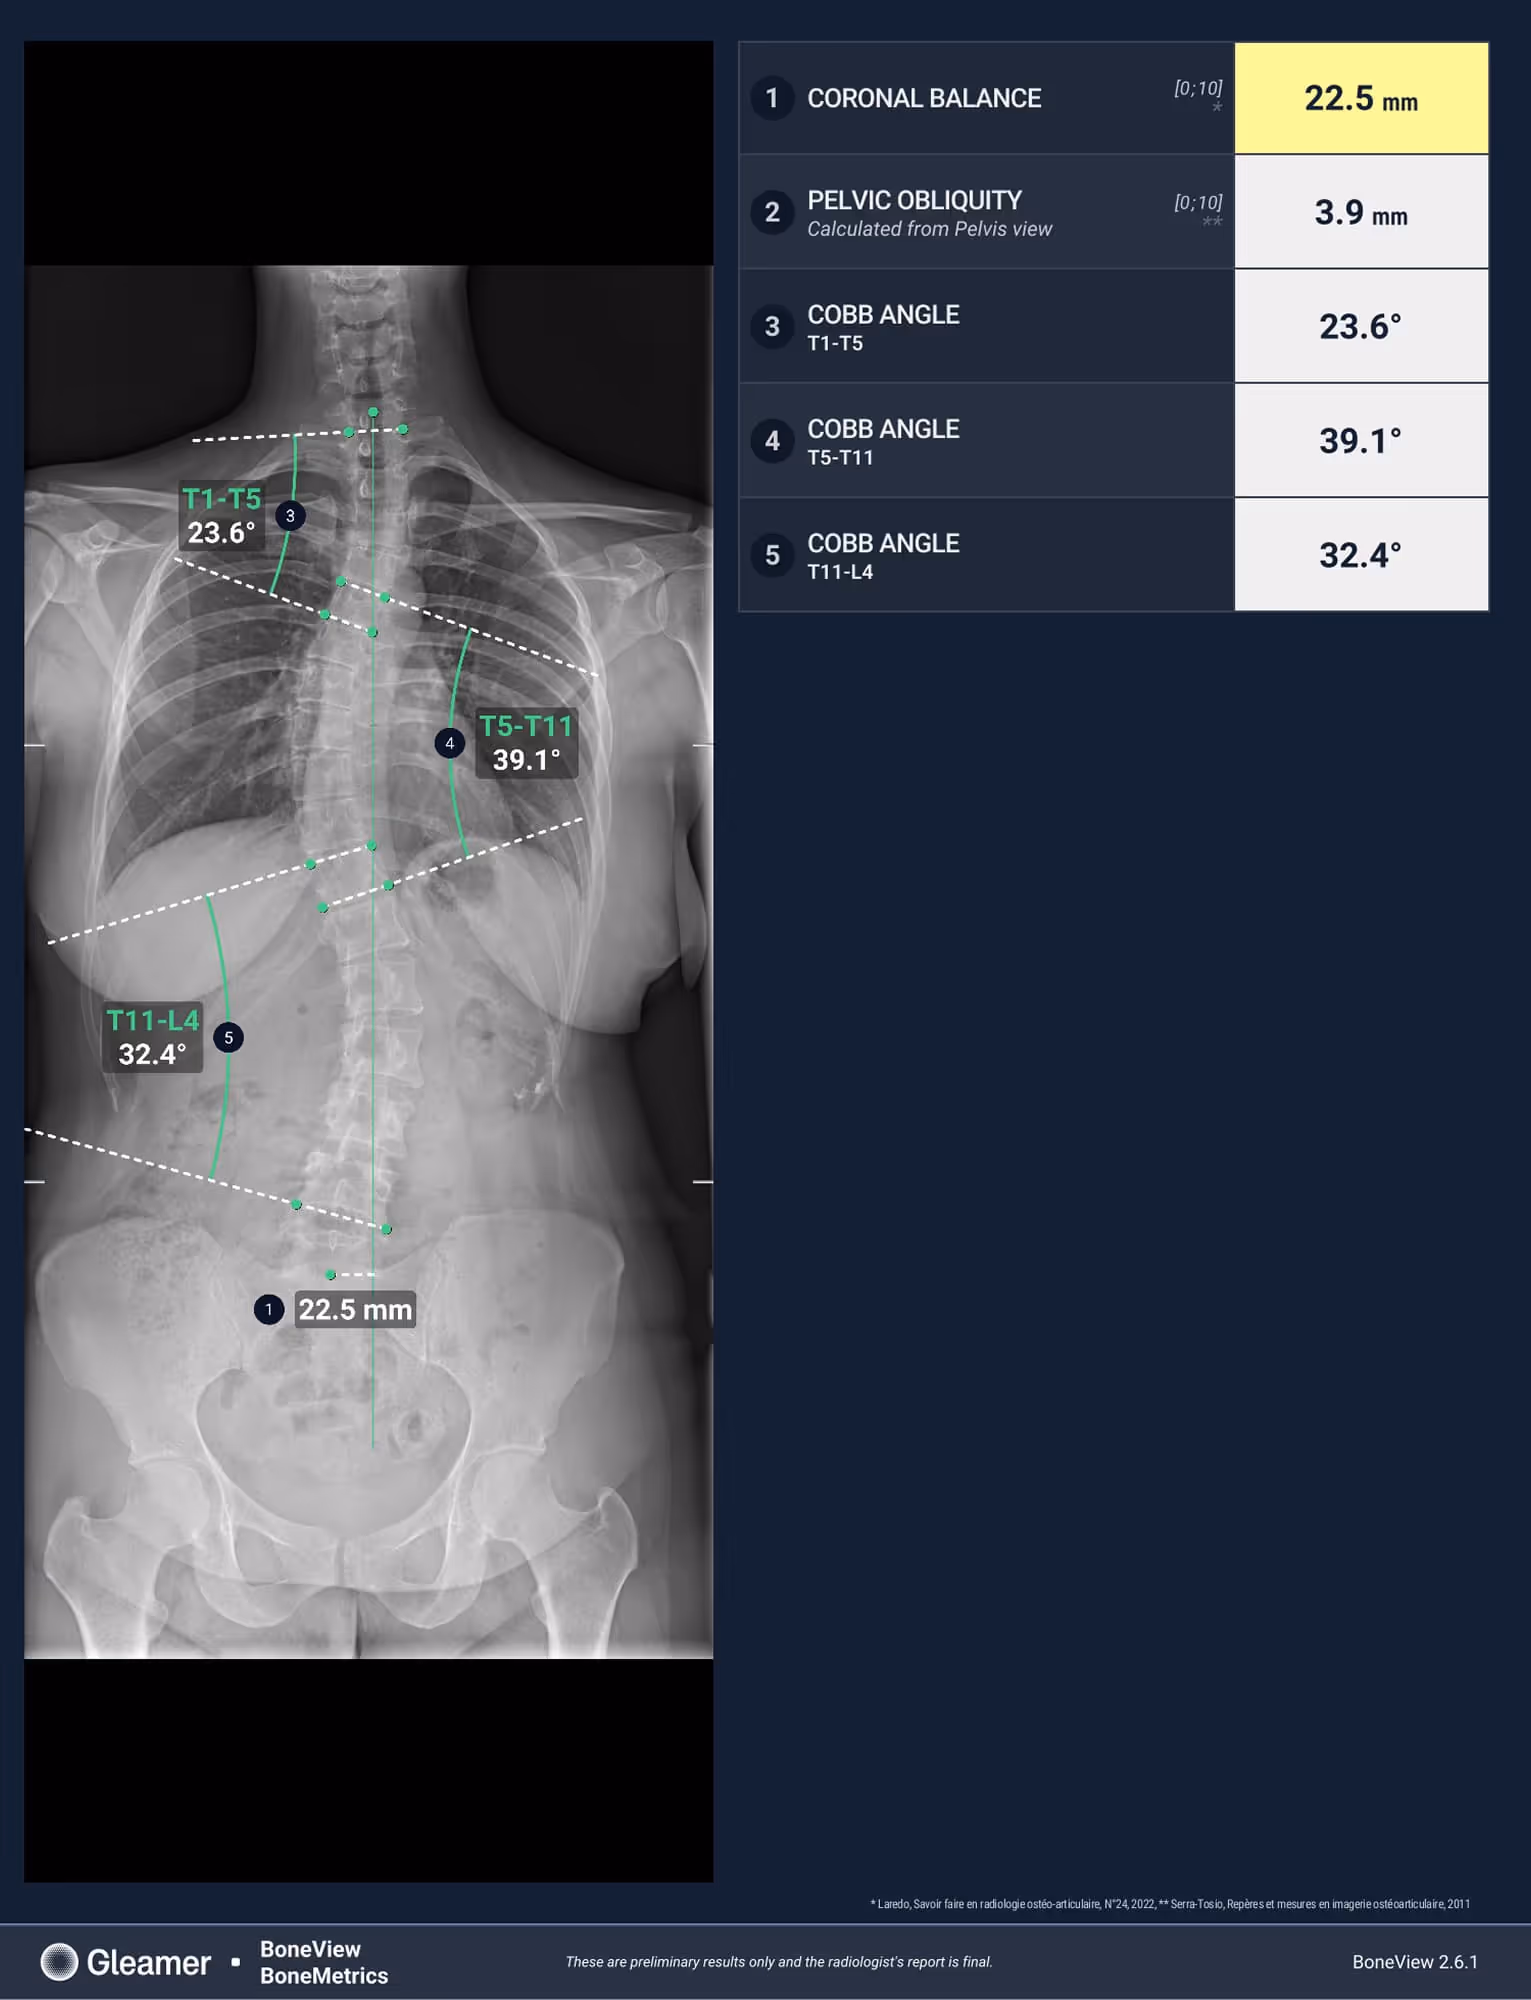

A 30-year-old female presenting with dorsal main, and a history of untreated scoliosis in childhood.

BoneMetrics identified three distinct Cobb angles, consistent with a triple curve scoliosis.

Cobb angle

Pelvic obliquity

Coronal balance